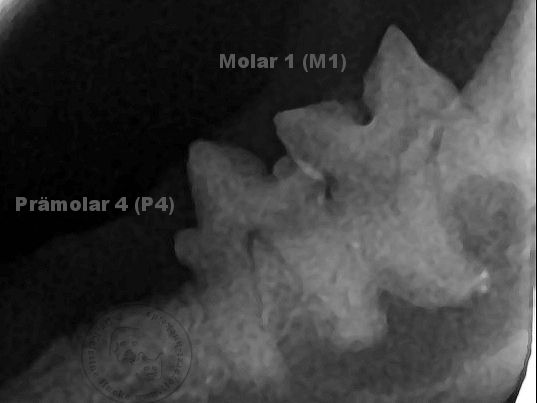

Hier die Röntgenaufnahme der anderen Unterkieferseite, man sieht deutlich die kräftigen Zahnwurzeln

Der Pfeil zeigt den aufgelösten dunkleren Wurzelbereich, darunter ist aber auch noch ein intakter Wurzelteil in der gestrichelten Linie sichtbar, eine typische FORL-Erkrankung